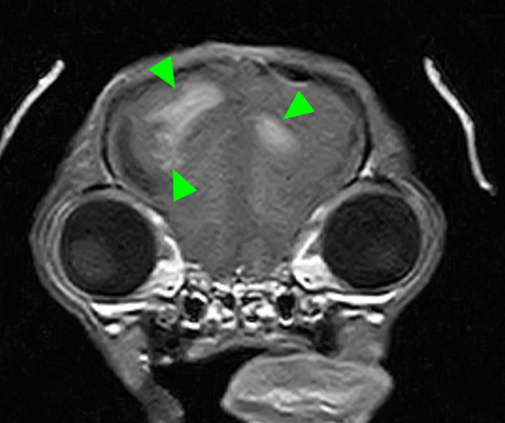

本症例のMRI検査所見:

・前頭葉白質領域(右>左)および右側大脳白質領域(側頭葉・後頭葉)にT2強調画像/FLAIR画像で高信号を示し、一部造影増強を示すびまん性の所見を認める。この所見は、DWI画像で高信号を示し、ADC-mapで大半は等~低信号を示す。

・透明中隔は欠損を疑うが、顕著な側脳室拡大を疑う所見は認められず、脳溝も明瞭である。